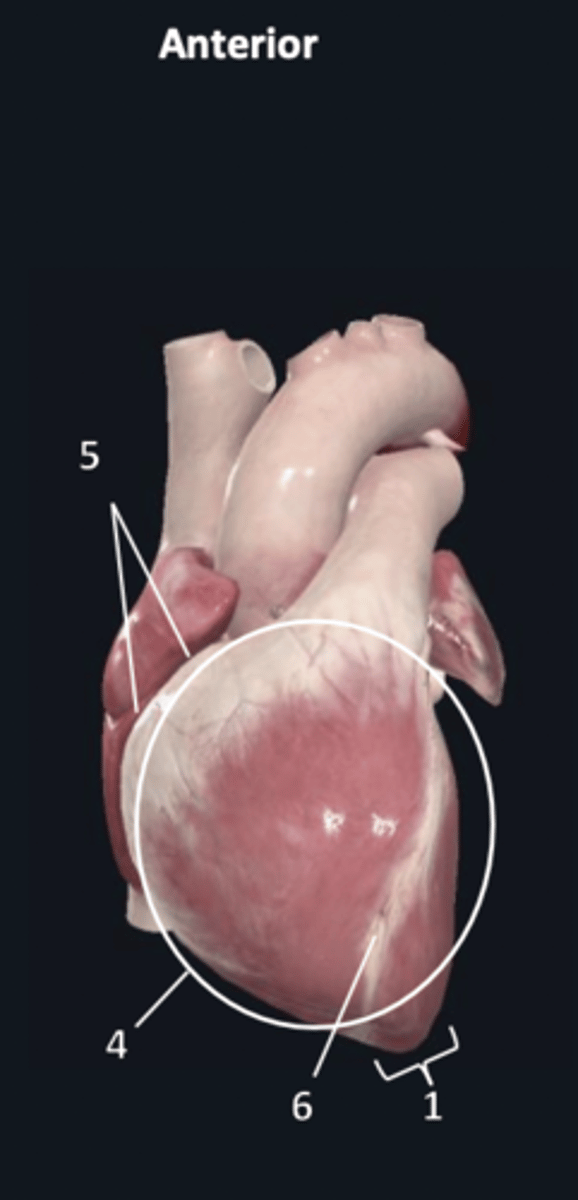

sternocostal surface

4

atrioventricular groove

5

anterior interventricular sulcus

6